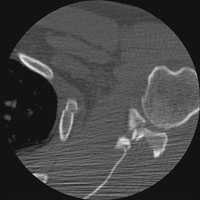

- Click on the image for a larger versionBAxial CT. This also shows the comminuted intraarticular fracture of the glenoid.

- Click on the image for a larger versionCAxial CT. This image shows a Bankart fracture.